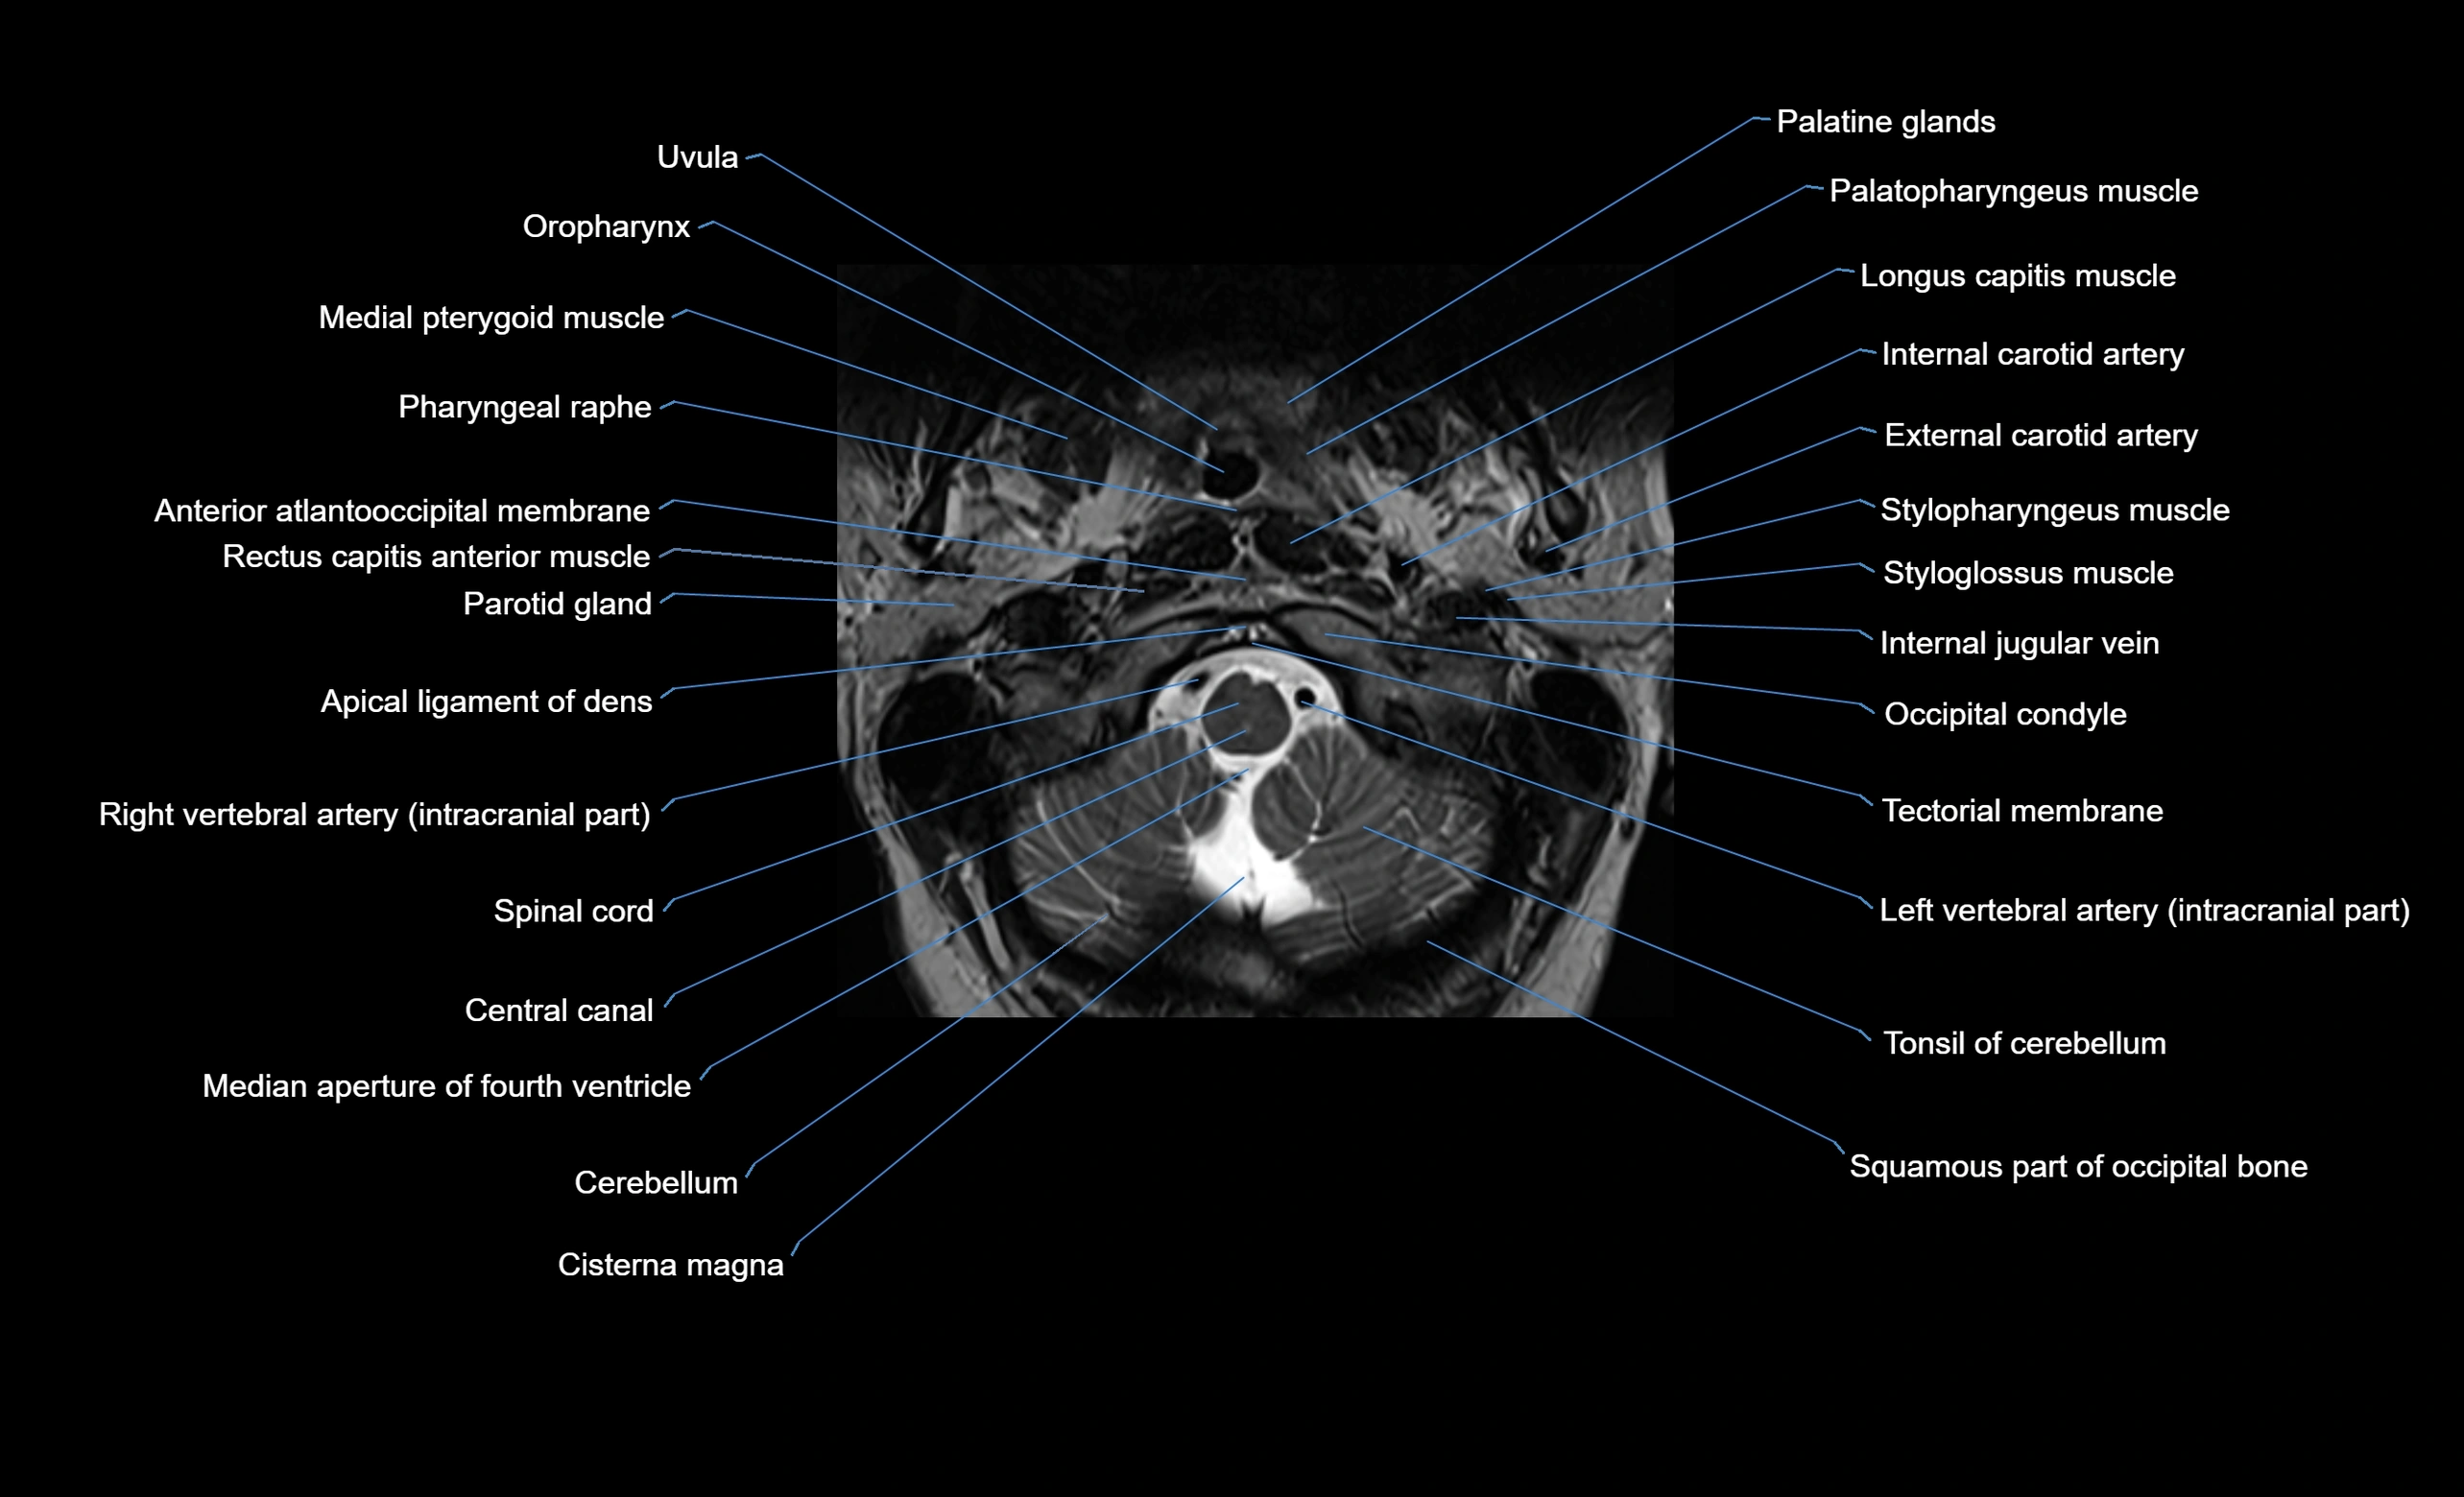

MRI appearance

T1-weighted images:

• Annular epiphysis: Low signal cortical rim at the vertebral margin

• Adjacent marrow: Intermediate-to-high signal in the vertebral body

• Disc interface: Clear delineation between bone and annulus

T2-weighted images:

• Annular epiphysis: Low signal intensity line

• Endplate cartilage (in younger patients): Intermediate signal

• Intervertebral disc: High signal nucleus pulposus

STIR:

• Annular epiphysis: Low signal cortical rim

• Adjacent marrow: Suppressed fat signal with preserved bony outline

• Utility: Highlights marrow and endplate interface in developing spine

MRI image

image